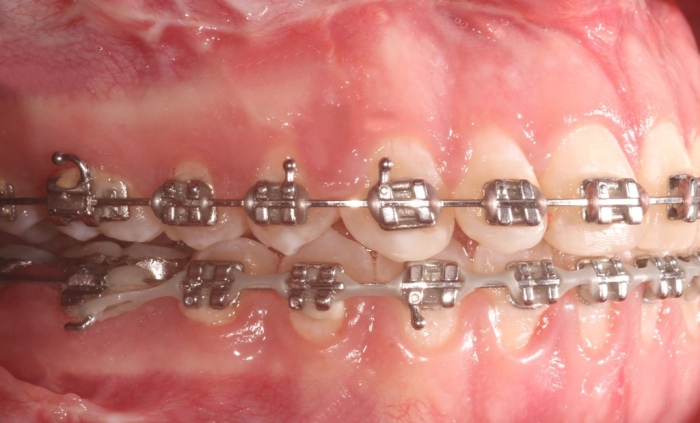

Mordida inicial - Clínica Cliniface

Mordida inicial